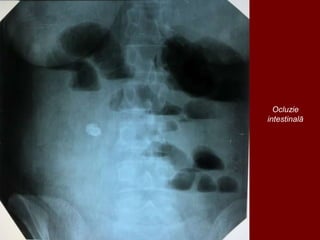

Ocluzie

intestinală